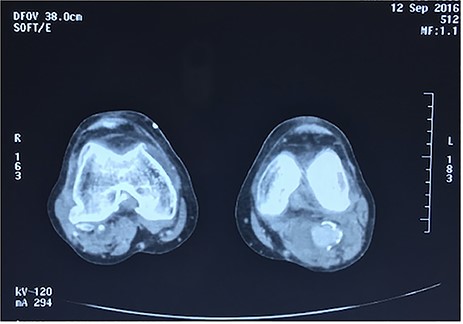

Approval for retrospective reports is not required by our institutional review board. This study is in accordance with the principles of the Declaration of Helsinki. A 77-year-old man with multiple comorbidities, including coronary vascular disease, hypertension, dyslipidemia, previous right carotid endarterectomy, and endovascular aortic repair (in 2011), was referred to our unit for evaluation of a retropopliteal pulsatile mass. He had undergone infra-popliteal stenting 18 months earlier, to treat peripheral arterial disease with severe left claudication. The procedure was performed at another vascular institute, and the stent type was unknown. Physical examination revealed the presence of a femoral and popliteal pulse and the absence of tibial pulses; at admission, the ankle–brachial index was 0.8. According to the patient, he had noticed the mass in the last 2 months prior to admission, but the absence of pain delayed his presentation to the hospital. An ultrasound scan was performed on admission and revealed a large popliteal pseudoaneurysm with normal flow present distally, and fracture of the stent was confirmed by computed tomography, which also detected a 4.2 cm dilatation of the left popliteal artery (Figs 1–3).

Angiotomography revealed fracture of a stent deployed in the popliteal artery and a pseudoaneurysm formation of size 4.2 cm at the part of stent fracture.

Angiotomography of the popliteal region highlighted the complete stent fracture and a large pseudoaneurysm formation.

Angiotomography showing a fractured stent and pseudoaneurysm at the site of the fracture.